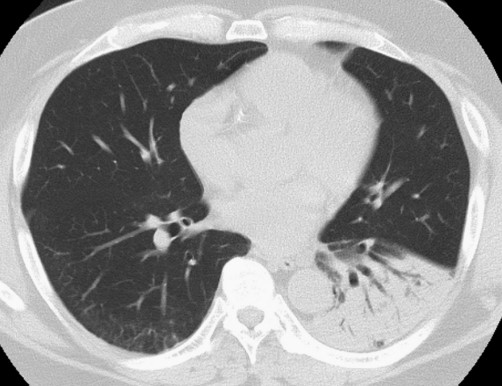

患者體格檢查無明顯異常。血液檢查顯示C反應蛋白水平升高,1.80 mg/dL;天冬氨酸轉氨酶輕度升高,55 U/L;丙氨酸轉氨酶升高,58 U/L。其他指標無明顯異常。血清β-D葡聚糖、人類免疫缺陷病毒(HIV)血清學和結核感染T細胞檢測(T-SPOT.TB)檢查均為陰性。高分辨率CT掃描顯示左肺下葉實變伴空氣支氣管征(圖1)

圖1 高分辨率CT掃描顯示左肺下葉實變伴空氣支氣管征